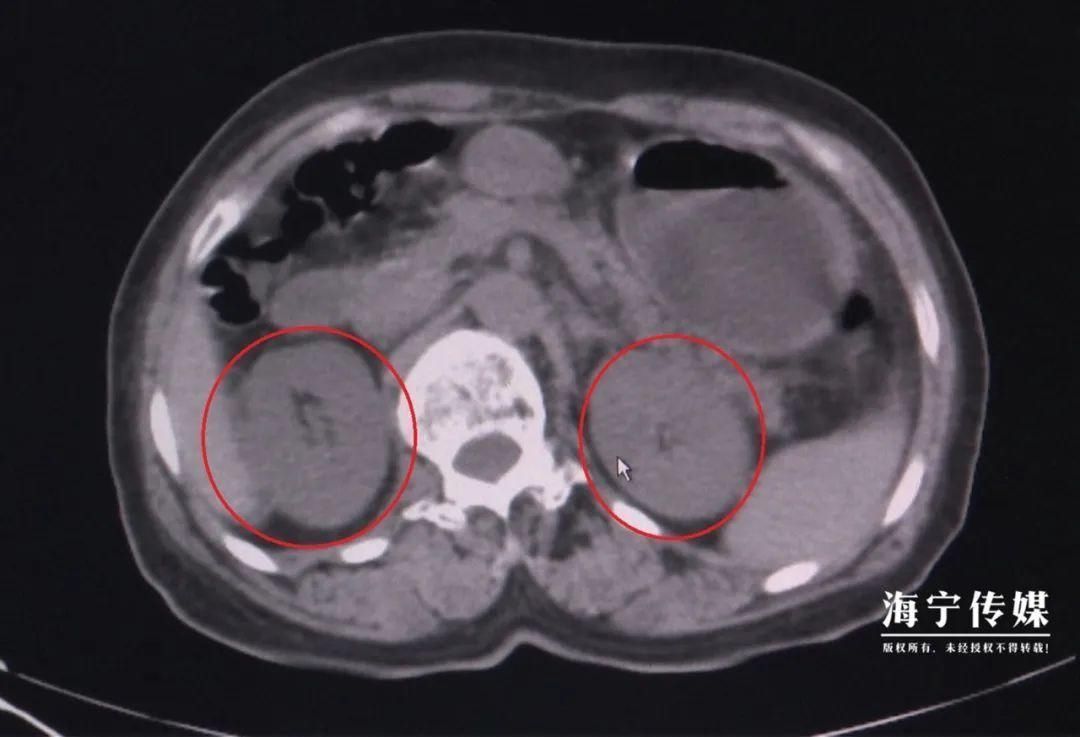

▲红圈部位为双肾肿胀 吃个刀豆怎么就中招了? “这是典型的食物中毒!”医生说,刀豆中含有生物碱,加热可分解。但李阿姨吃了整盘没烧熟的刀豆,毒素吸收导致急性肾功能衰竭,不能正常产生尿液,体内肌酐、尿素、氮尿酸等代谢废物无法排出。反映肾功能的肌酐指标一度飙升到600多,超出正常值上限的6倍。 如不及时治疗,有突然心跳停止、血循环消失、休克的危险。住院后,李阿姨接受了血液透析治疗。